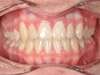

Avant

Après